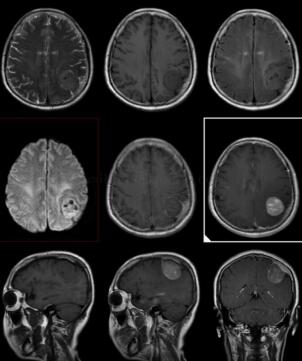

图1 左侧顶叶颅板下方见一较大类圆形占位,与硬脑膜相连,大小约3.0cm×2.8cm,呈稍长T1,稍长T2信号,其内信号不均匀,见较多点状长T1、短T2信号影。增强扫描病变不均匀明显强化,邻近脑实质呈受压改变

轴外肿块,多为均质性,可有坏死、囊变和钙化,易引起邻近骨质增生或受压变薄膨隆,病灶周围不同程度水肿(压迫引流静脉)。CT显示肿瘤界限清楚,大多数脑膜瘤实质部分为高、略高或等密度。MRI上与灰质相比,典型者各序列均为等信号,或呈T1略低、T2略高或高信号;约10%肿瘤信号变化不定。可见血管流空信号。增强扫描肿瘤实质部分明显、均匀强化。

可具有良性脑膜瘤CT/MRI表现,肿瘤边界不清、形态多不规则,如轮廓呈分叶状、结节状或锯齿状,肿瘤坏死、囊变较常见,恶性者出血可见,钙化极少见。肿瘤邻近骨质增生和(或)破坏,甚者扩展至颅外组织,病灶周围可有中、重度水肿围绕。肿瘤密度、信号不均匀更为常见,CT显示略低或等密度,少数为低、等混合密度。MRI扫描T1WI呈等或低信号,少数为低、等或等、高混杂信号,T2WI则为等或高信号。增强扫描多呈斑片状不均匀明显强化,邻近脑膜强化呈粗短不规则形,“脑膜尾”征。